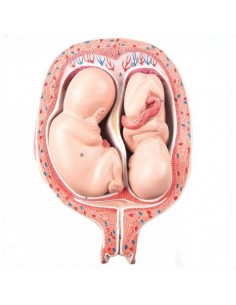

3B Scientific. Kit d'enseignement, système de reproduction femelle W40214

3B Modèle scientifique et anatomique du développement de l'embryon en 12 étapes VG391